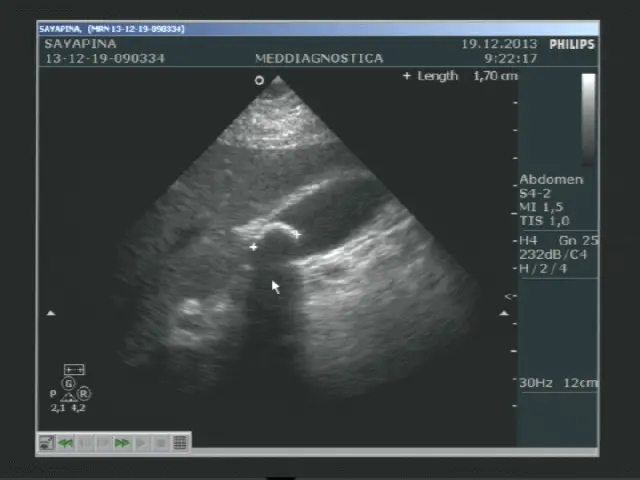

Лікар наносить на область живота спеціальний гель, після цього водить по шкірі ультразвуковим датчиком. На моніторі вимальовується картинка області дослідження. Лікар робить помітки, заміряє розміри і щільність органів, вивчає клінічну картину.

Дослідження проводиться на сучасній апаратурі з використанням передових технологій, що мінімізують похибки вимірювань. Доктора, які проводять дослідження мають відповідну кваліфікацію.